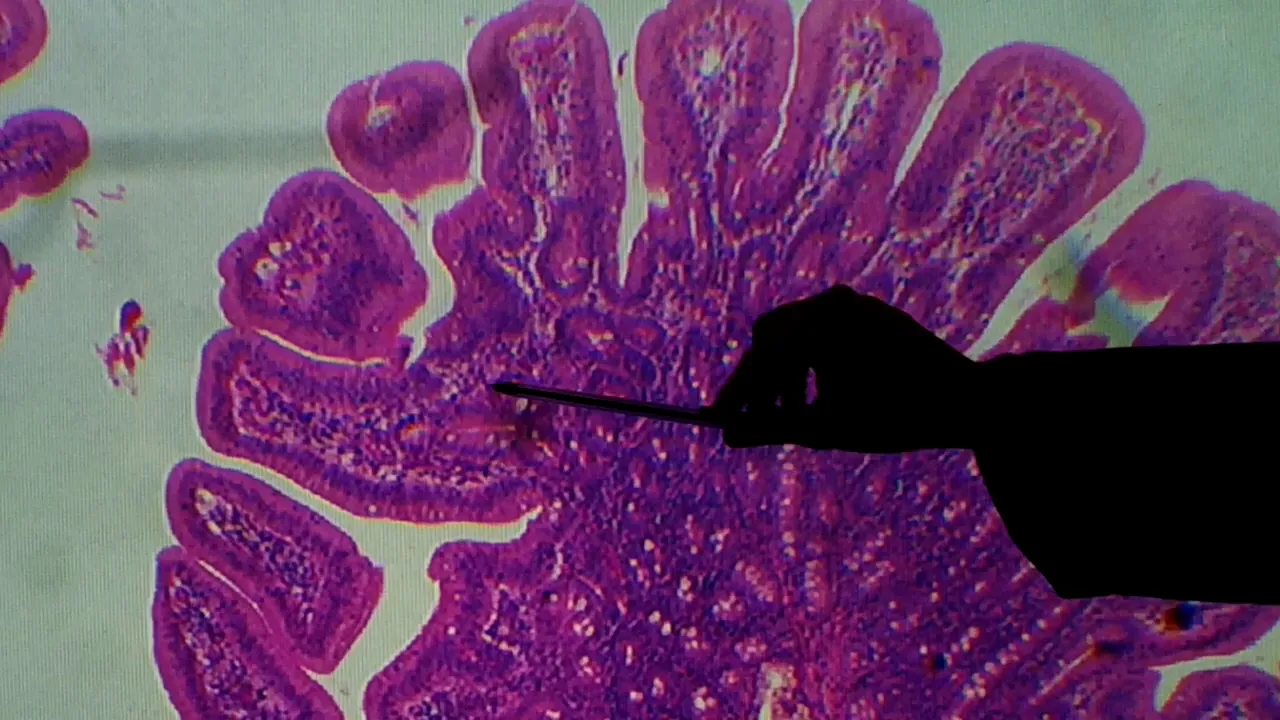

temos um corte transversal do dendo que a opção inicial do intestino delgado lembrando tem rodeia juno e milho que também apresentam algumas características biológicas diferentes mas o objetivo dessa vídeo-aula falar de uma maneira mais geral então olha hoje estou usando um modelo como esse aqui é o corte dele inteiro amores o homem e as quatro camadas que nós já descrevemos camada no cosa submucosa essa mais falha daqui muscular externa ea serosa numa travessa momento está arrebentada essa imagem externa de estômago intestino delgado também apresenta várias obras que são as pregas intestinais que também contou com

da mesma maneira que a gente numa lâmina de estômago estas praias apresentam um eixo de ter sido o motivo que assumimos rosa e certamente está nada honrosa agora com a diferença de todo o trato gastrointestinal que só existe aqui no caso do intestino delgado é a presença dessas projeções aqui essas nações nada um posa ou seja de pele na própria apenas que a gente chama de velocidades essas velocidades servem para aumentar a superfície de contato da célula com o meio externo e com isso vai ter uma superfície maior contato pra a solução e também para

a gestão vou colocar agora no aumento maior para a gente ter uma idéia de com essa estrutura se organizam a só mostrando aqui que a gente pode ter com o corte normal como está aqui como também pode encontrar alguns fragmentos é alguns cortes transversais que parecem fragmentos aqui duas velocidades sykora foi em três dimensões a gente pega apenas na superfície semelhante isso coisa aqui é o ideal na hora de observar landu é procurar uma região que ele esteja inteiro obrigado aqui ou na velocidade ou na prega isso é uma prévia cada projeção uma novidade ou

nessa região que estão colocando agora quanto maior a questão aumento de 40 vezes a gente está vendo a borda de uma pedra aqui do destino como eixo central de submucosa e revestindo certamente camada no coisa o etéreo que reveste a gente consegue observar nessa região é uma bactéria cilíndrico com o selo halal tão simples que até apenas uma camada ac atacou logo abaixo do ministério tem a a lâmina própria que o tecido conjuntivo falso e nesse caso do intestino ele tem bastante saúde tem muitas células linfóides espalhadas aqui pode encontrar em força popular mostra uma

prova favor espalhados por várias regiões essa taxa aqui serviço tração é isso aqui desse lado a coisa tá aqui pra cima tem algumas reservas de nações são projeções externas desse critério e alana própria camada nebulosa é trazer na geração e rosa é o que a gente chama de velocidades então isso aqui é uma velocidade e só que outra velocidade aqui é outra essas já as imaginações traçar uma linha ascendente das funções da etérea aqui imaginando forma as glândulas intestinais ou plano os libertou que o critério que vai ser o mesmo também servir ea gente também

um coisa aqui embaixo essa faixa rosa desse lado esse aqui é a camada muscular da proposta então aqui é o limite da camponesa muscular na mucosa aqui a moção plano larfaoui tele 5 cilindros são os caras se forme lembrando que se trata de links em cada sala outras recebe o nome de iperó se do inter o passado intestinal com capacidade de absorção por causa da secreção e absorção que também necessitam consensos digestivas além das meninas que qualquer modelo alega ser observado cedo ou culpa grave e aqui nesse eixo central disso de rosa pode ser um

critério que equivale ao território visceral foto terry pavimento simples e uma camada de tecido com o objetivo então voltar agora para a camada um coça das pampas e colocar um aumento maior para a gente ver mais deixar essas características das células que 90 de cem vezes mostrando em detalhes curiosidade e aqui que é uma ampla a imaginação do comando na velocidade ou por curiosidade e as reservas nações informando aos planos orlando anos investi nice ou bancos de libertar sambando os populares embora não consiga ser bem limite delas aqui aqui já dá pra ver melhor formato

das selvas a questão de critério e critério simples uma única camada de células e as células são cilíndricas e elas são chamadas de iperó sitos faz células especializadas na função e também na secreção algumas enzimas [Música] depois de almoçar com medo maior elas também vão apresentar uma borda espuma aqui somente para velocidades que também favorece o aumento da superfície de contato e absorção é interessante diferenciar aquele muita gente confunde o que é uma prega o que é uma velocidade e fica uma bíblia velocidade todas essas estruturas têm intenção de aumentar a superfície de contato no

caso da prega é o que mostrou um aumento menor é o conjunto é a dobra do aclamado subiu roça com a mucosa junta as duas são o eixo pessoas rosa e envolta em causa era bem grande dá pra ver com o nosso pacote também virou realidade é uma projeção apenas da camada aquosa e velho elano na própria daquele tecido conjuntivo chefe células de defesa também m provê-los idade são projeções de cada célula erótico aqui projeções da membrana no citoplasma não dá pra ver esse aumento agora ou depois eu coloco maior pra gente ver meu é

essa bota mais escura que fique para sempre com novidades e isso tudo aqui uma velocidade é uma dobra da camada mucosa o eixo de lâmina própria tecido conjuntivo frouxo e aqui são os que falam na própria a gente observa tem vários fatores são filhos jack já que facilita a dissolução e também muita saúde e defesa aqui vai estar misturado e force uma trofa com as mostras é comum em várias dessas células essa vitória estados unidos e organizando lá na mais trabalho formando novos ou políticos novos uniformes e elas fazem parte de um conjunto de tecido

linfóide associado à mucosa mal tive como a gente queria falar de outra ó nesse caso especializada do intestino intestino inglês que antes estava vencido e porte associadas investiram grandes daí a sigla ficaria gault vamos fazer um pacto para finalizar voltei aqui ó aumento de 40 vezes numa região que dá pra ver as quatro camadas lembrando aqui essa dobra da sudema coisas a imaginação é uma prega revestida por camada rosa e aqui aqui dá pra ver melhor teve um corte mais o público cada imaginação de uma coisa investida critério é uma velocidade e tele o clube

na própria cada imaginação aqui na camada córnea é uma glândula landa intestinal aqui a muscular da mucosa que está um pouco acidentado e na camada subclávia como essa média moderna onde oito professoras bom demais se fosse já não ele queria só desse coletivo e muscular externa lulista com a amada circular interna e longitudinal estréia tanto entre as duas do sexo nervoso união e térmico e mais internamente é que está arrebentando mas a mesma cuba da mesma maneira que nós vimos na lâmina de estômago é acamada serosa que equivale a camada visceral no peritônio então é